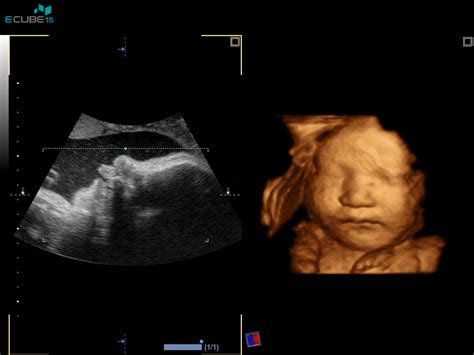

- Vpliv na otrokovo razvitost: Kot je omenjeno, kajenje med nosečnostjo upočasnjuje razvoj otroka. Ta upočasnjeni razvoj se lahko odraža tudi v nezrelosti prebavnega sistema, vključno s šibkejšimi sfinktri, kar bi lahko povečalo nagnjenost k refluksu. Otroci, katerih matere so kadile med nosečnostjo, imajo lahko manj razvit centralni živčni sistem, kar lahko vpliva na koordinacijo požiranja in prebave. Ultrazvočni 4D posnetki nosečnic, ki so jih posneli v James Cook univerzitetni bolnišnici v Middlesbroughu, so pokazali, da so se otroci mater, ki so kadile, svojega obraza in ust v maternici dotikali veliko pogosteje kot otroci mater, ki niso kadile med nosečnostjo. Strokovnjaki menijo, da je iz tega jasno razvidno, da prihaja pri plodu kadilke do upočasnjenega razvoja centralnega živčnega sistema plodu.